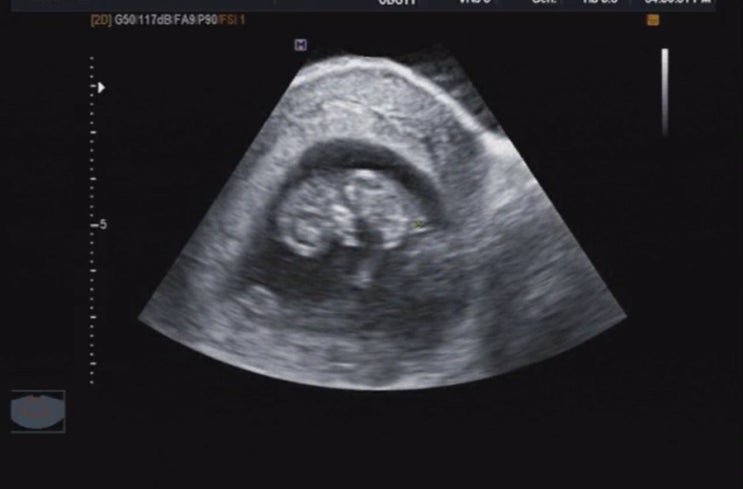

초특급 둘째출산 37주2일

율동이 36주까지 채워 일하고 37주엔 출산준비를 하려했으나, 조리원 마지막날 출산후기로 돌아온 율동애미...

율동아 안녕,

둘째를 가지고 초반 증상?이나 임신 주수에 따라 어땠는지 나도 내 블로그를 참고 했다 아이러니하게도 하...